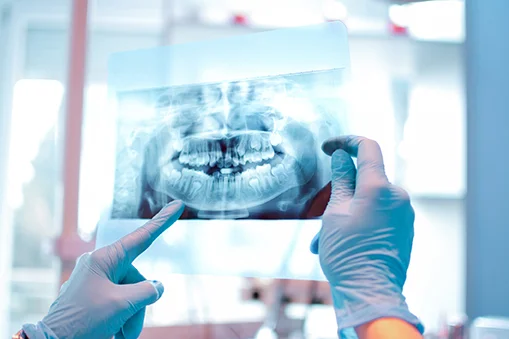

diagnostic corect și plan de tratament personalizat;

utilizarea unor tehnologii moderne și instrumentar de ultimă generație;

Este important ca fiecare pacient să efectueze un consult stomatologic periodic, deoarece depistarea din timp a problemelor poate reduce necesitatea unor intervenții complexe.